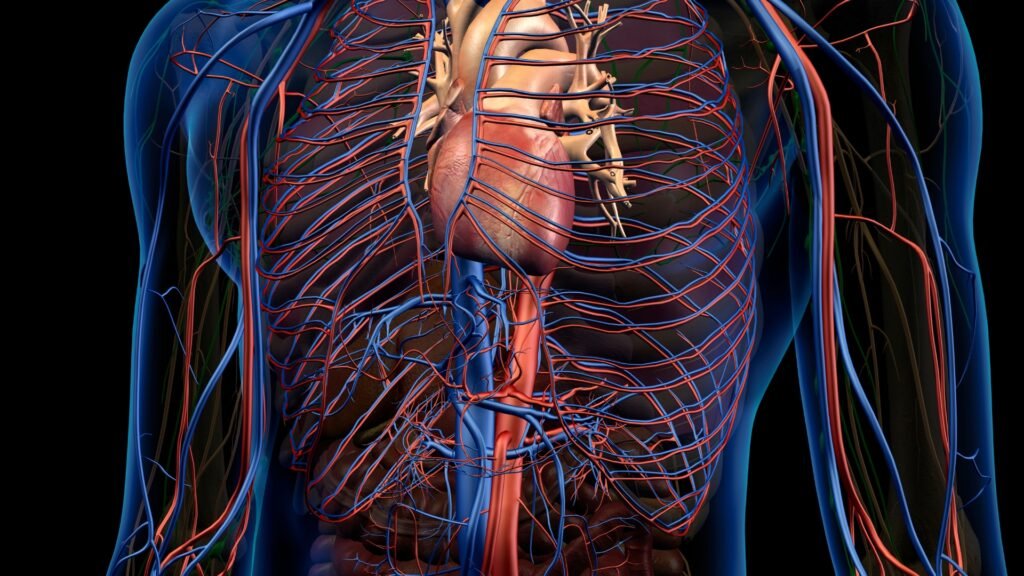

Um técnico ou médico especializado em ultrassonografia vascular conduz o Doppler colorido de aorta e ilíacas. O paciente se deita confortavelmente, enquanto um gel condutor é aplicado na área abdominal para garantir que as ondas sonoras do transdutor penetrem de forma eficaz. O técnico move o transdutor ao longo da pele, capturando imagens detalhadas das artérias. A tecnologia Doppler adiciona uma codificação de cores às imagens, o que facilita a visualização do fluxo sanguíneo e a identificação de áreas com fluxo alterado.

- Diagnóstico Preciso de Aneurismas: Este exame detecta dilatações anormais nas artérias, conhecidas como aneurismas, que podem levar a rupturas fatais se não forem tratadas.

- Identificação de Estenoses: Ele permite visualizar estreitamentos nas artérias que podem comprometer o fluxo sanguíneo. Identificar essas estenoses possibilita uma intervenção precoce.

- Avaliação Detalhada do Fluxo Sanguíneo: O exame oferece informações detalhadas sobre a velocidade e a direção do fluxo sanguíneo, cruciais para um diagnóstico preciso e um plano de tratamento adequado.

O Doppler colorido de aorta e ilíacas é uma ferramenta vital para o diagnóstico e monitoramento de condições vasculares. Ele fornece informações detalhadas e precisas sobre o fluxo sanguíneo e as artérias, o que pode fazer uma grande diferença na sua saúde. Para saber mais sobre como este exame pode beneficiar sua saúde vascular, entre em contato e marque uma consulta com o Dr. Leonardo Pacheco.